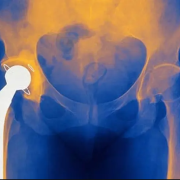

جراحی تعویض مفصل

جراحی تعویض مفصل ران و لگن چگونه انجام میشود؟ تعویض مفصل ران یکی از جراحی های پیچیده است که توسط متخصص ارتوپدی انجام می گردد، در حین این جراحی، جراح مفصلی که دچار آسیب دیدگی شده باشد را برداشته و به جای از یک مفصل مصنوعی استفاده می نمایید. در این مقاله قصد داریم همه …ادامهی مطلب »